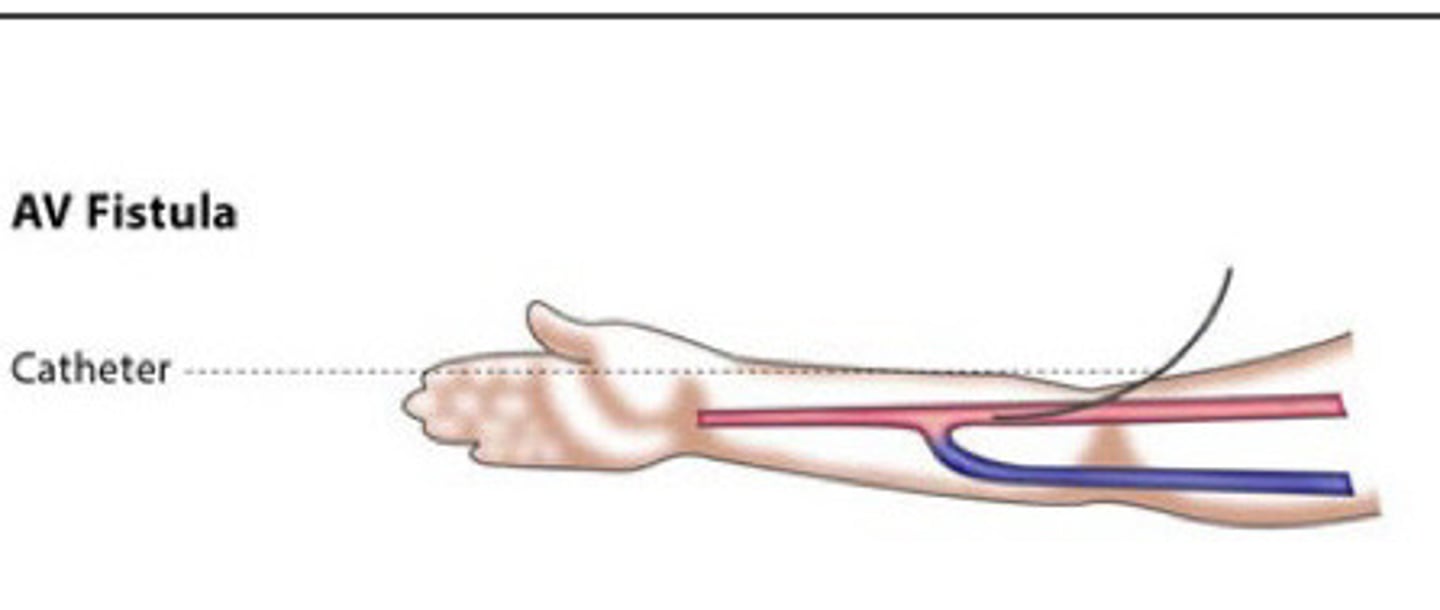

Hemodialysis

What does this image show

Create an AV connection to facilitate high volume flow with superficial access

What does a fistula and a graft both accomplish

Direct anastomosis created between a artery and vein (have to go in surgically and create the fistula)

Describe a fistula

Fistula